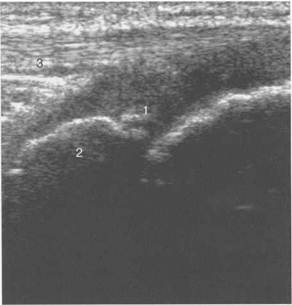

Рис. 19.120. УЗИ коленного сустава. Начальная

1 — начальные ядра оссификации бугристости; 2 — эпифиз большеберцовой кости; 3 — собственная связка надколенника.

различного возраста собственная связка надколенника прикреплется к неполностью или полностью оссифицированной бугристости большеберцовой кости, имеющей различную эхогенность и структуру в зависимости от возрастного этапа оссификации (рис. 19.119— 19.123). При этом эхоструктура самой связки с возрастом не меняется. Постепенно с возра­стом несколько меняется эхогенность связки (от меньшей до более высокой).